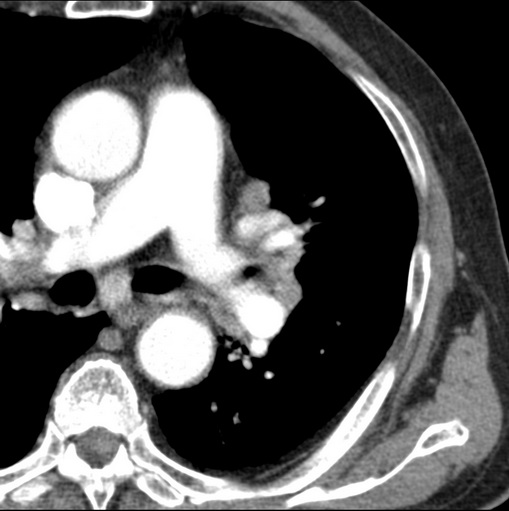

男性患者 81岁 咳嗽 咳痰 咯血

肿块贴近左肺门,包绕左上肺动脉,形态不规则。肿块增强扫描中度强化。纵膈内主动脉弓左旁间隙、气管隆突前、下间隙见多枚淋巴结影。综上考虑左侧中央型肺癌可能性大。图片没有完整上传,尤其是左肺上叶支气管分支层面没有上传,因此不好判断是叶支气管中断还是段支气管中断。另外,下图红色部分所示是“黏液支气管征”吗?